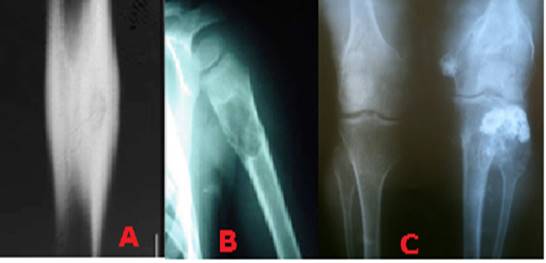

Se debe realizar una adecuada exploración clínica para saber las condiciones que se encuentra el paciente, es importante conocer el motivo de consulta pues ello a veces nos puede llevar a un diagnóstico, por ejemplo, el dolor nocturno que se alivia con la aspirina puede hacer pensar en el osteoma osteoide, 16 el niño que estaba jugando pelota y al lanzar siente dolor en el brazo con aumento de volumen e impotencia funcional, se puede pensar en un quiste óseo solitario o esencial. 17 En la palpación, un paciente con múltiples tumores duros no movibles y antecedentes familiares con el mismo cuadro clínico, puede ser una exostosis múltiple hereditaria (Figura 1). (18

Las lesiones óseas menos agresivas son la tipo I o geográficas de forma ovoide y a su vez, se dividen en tres subtipos según las características de sus bordes: A. Bordes nítidos con anillo esclerótico. B. Bordes nítidos sin anillo. Lesión lítica de bordes mal definidos. Las lesiones tipo IA son las menos agresivas, las IB, son de naturaleza indeterminada y las IC, las de mayor agresividad. Las lesiones tipo II y III son lesiones no geográficas y de bordes mal definidos (Figura 2).

Las lesiones óseas tipo II se describen como lesiones apolilladas y se componen de múltiples focos osteolíticos que varían en forma y tamaño. Las lesiones óseas tipo III son las más agresivas y se describen como lesiones permeativas, múltiples y de carácter lítico, por lo general, sin áreas de respeto entre las mismas (Figura 3). (22